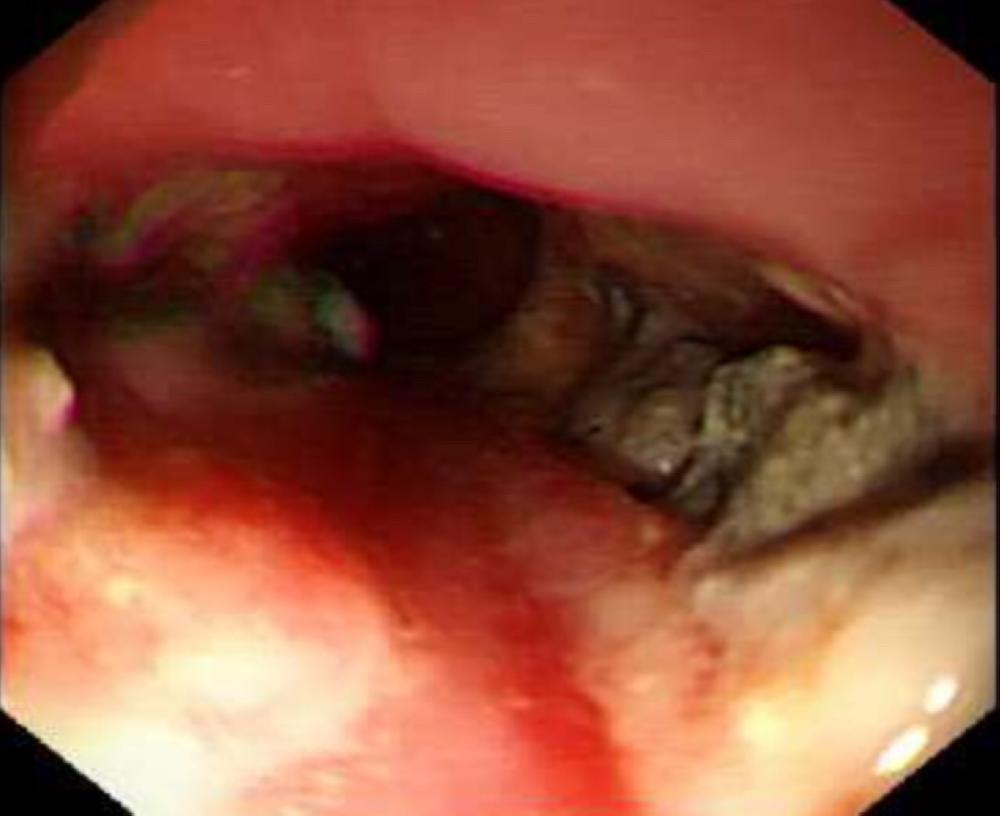

وأوضح استشاري الجهاز الهضمي بمستشفى الأطفال الدكتور موسى الخرمي بأن بلع الطفل للبطارية أسفر عنه تهتك أنسجة المريء وسبب تقرحات عميقة، مشيرا إلى أن الحالة تم التعامل معها، والطفل خرج من المستشفى بحالة صحية جيدة.

وقال سيتم متابعة المريض في العيادات الخارجية لمتابعة أي مضاعفات مستقبلية بعد ابتلاع البطارية ومنها تضييق المريء، وقد أجريت العملية بمشاركة الدكتورة دلال البقمي والدكتورة ريده فرزات.